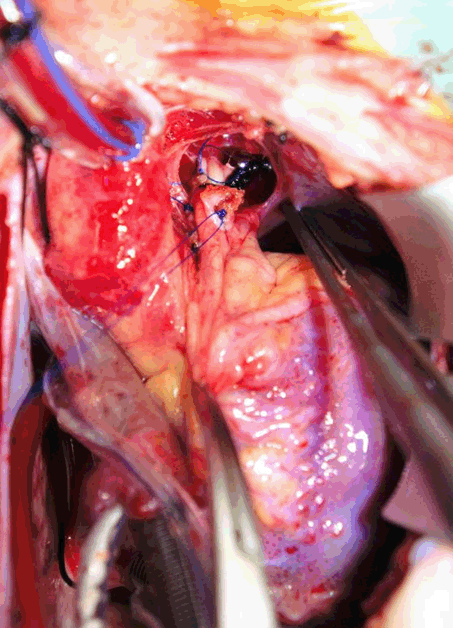

During her follow-up with cardiologist, no any additional echocardiographic change was noticed. Only during physical examination found to have grade 4 thrill with radiation to the neck. She was arranged for another cardiac catheterization for trail of closure once occluder devices became available in our center after 15 months from first catheterization. During the second catheterization aneurysmal change seen at the pulmonary end rather than aortic end of the PDA with aortic end 3.4 mm* midpoint 7.5 mm* pulmonary end 15.9 mm (Figure 2), so decision was made for surgical closure rather than trial of occlusion with a occluder devices (Figure 3).

Surgery was performed after nearly one month from catheterization, under general anesthesia and median sternotomy, cardiopulmonary by-pass without cardioplegia or circulatory arrest. Aneurysm found at the pulmonary end, simple ligation with non-absorbable suture material then aneurysmorrhaphy done at both pulmonary and aortic end with a pericardial pledged, smooth postoperative period without any complication. Immediate postoperative echocardiography showed trivial shunt across the PDA but with a week later no shunt was seen across the PDA anymore (Figure 4).

Figure 3: Aneurysmal dilatation at the pulmonary end.